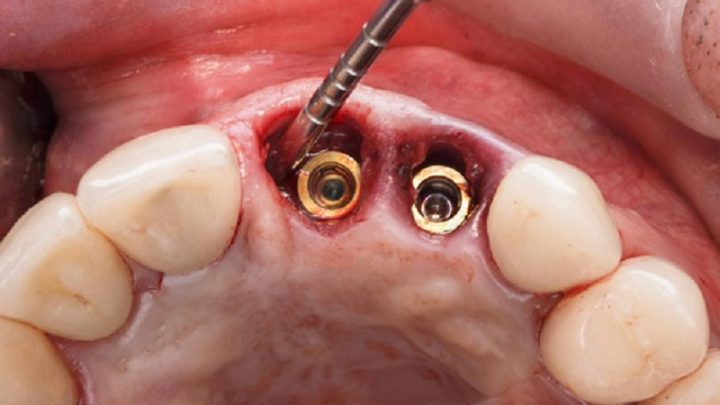

دکتر مهدی نعمت الهی ، به عنوان یک متخصص برجسته در زمینه ایمپلنت دندان، از روش های نوین و پیشرفته برای درمان بیماران استفاده میکند. یکی از این روشها، ایمپلنتهای فوری است که به بیماران این امکان را میدهد تا در همان روزی که دندان کشیده میشود، ایمپلنت جدید را نیز دریافت کنند. این تکنیک به ویژه برای افرادی که به دنبال بهبود سریع و زیبایی دندان هایشان هستند، مناسب است. همچنین، دکتر مهدی نعمت الهی با استفاده از تکنولوژیهای دیجیتال و تصویربرداری سهبعدی، دقت بالایی را در مراحل برنامهریزی و اجرای ایمپلنت ها فراهم میآورد، که منجر به نتایج بهتری میشود.

روش دیگری که دکتر نعمت الهی به کار میبرد، استفاده از ایمپلنتهای کوتاه و باریک است. این نوع ایمپلنت ها به خصوص در مواردی که استخوان فک بیمار به اندازه کافی ضخیم نیست، کارایی بالایی دارند. با بهرهگیری از این تکنیک، علاوه بر کاهش نیاز به پیوند استخوان، زمان درمان نیز به طرز چشمگیری کاهش مییابد. دکتر نعمتالهی با توجه به نیازهای خاص هر بیمار و با در نظر گرفتن شرایط فردی، مناسبترین راهکار را انتخاب میکند تا تجربهای راحت و کامیاب را برای بیماران خود رقم بزند.

در مرحله بعدی، جراحی ایمپلنت آغاز میشود که طی آن، پایه تیتانیومی ایمپلنت در استخوان فک قرار میگیرد. این عمل با دقت و تخصص بالا انجام میشود تا حداقل آسیب به بافتهای اطراف ایجاد شود. پس از نصب ایمپلنت، بیمار به مدت چند ماه تحت نظر قرار میگیرد تا فرآیند بهبود و ادغام ایمپلنت با استخوان فک به درستی انجام شود. در نهایت، زمانی که ایمپلنت به طور کامل تثبیت شد، دکتر نعمتالهی با دقت پروتز دندانی مناسب را بر روی ایمپلنت قرار میدهد تا زیبایی و کارایی دندانهای طبیعی را برای بیمار به ارمغان آورد.